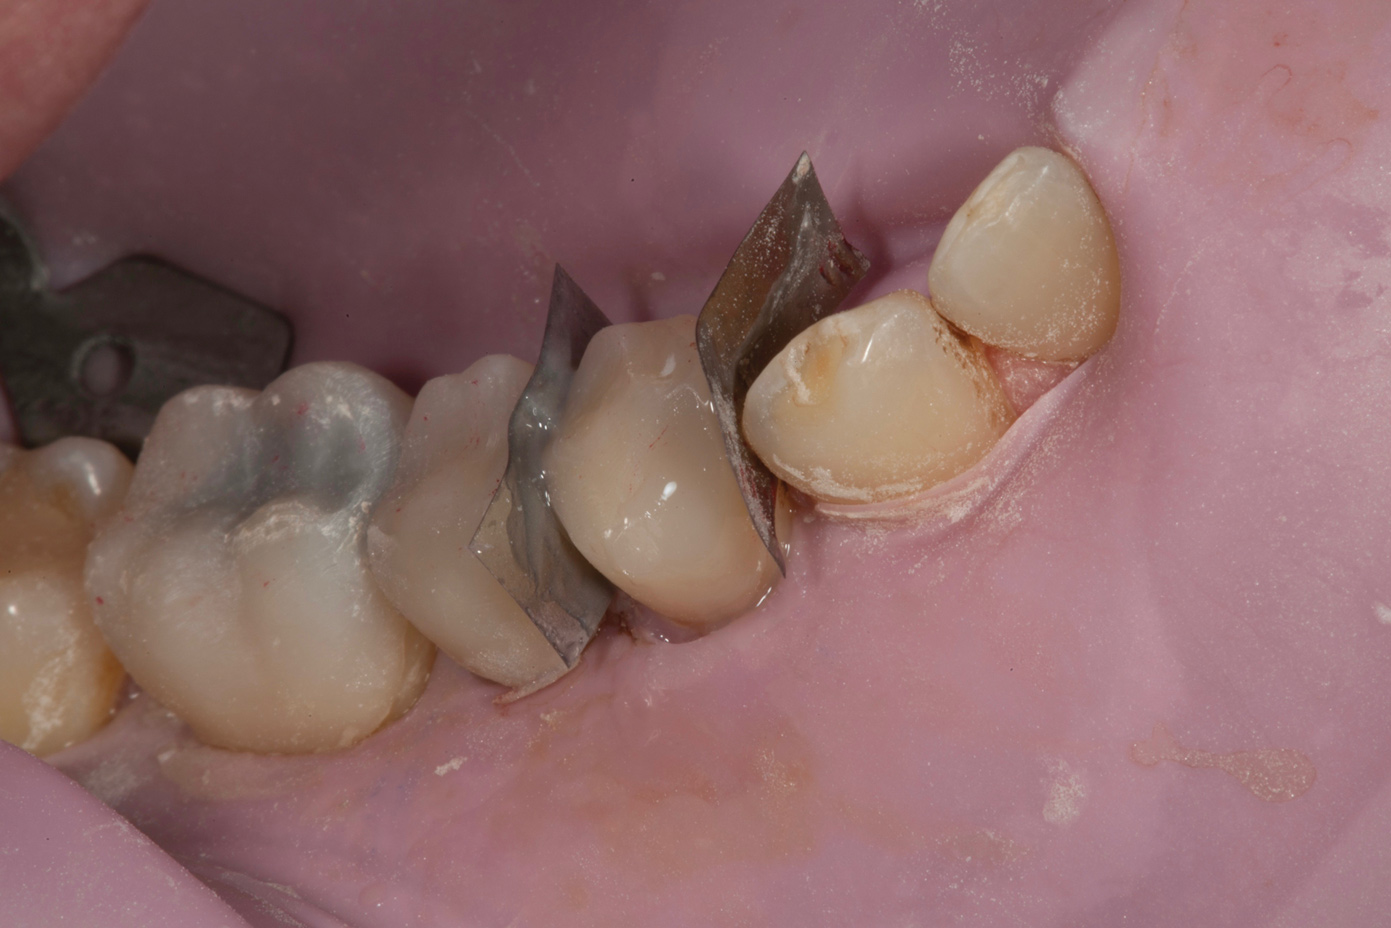

Fig 6. Fitting of prefabricated posterior units.

Figure 6

Following caries treatment and tooth preparation (Figure 6), teeth Nos. 4 through 13 were restored with direct composite veneers in stages (Figure 7 through Figure 9). Using a hybrid composite for the lingual shelf and dentin layer provides wear resistance and strength for the restoration.14,15 (The lowest wear rates for restorations and the opposing dentition occur with metal alloys, machined ceramics, and microfilled hybrid resin composites. Any adjusted and unpolished porcelain surface would elicit the most wear on the opposing teeth.11)After the composite veneers were finalized, a monolithic lithium disilicate crown was placed on tooth No. 12 during a subsequent appointment, and occlusal equilibration was carried out. Final photographs were taken a couple of weeks later (Figure 10 through Figure 14).